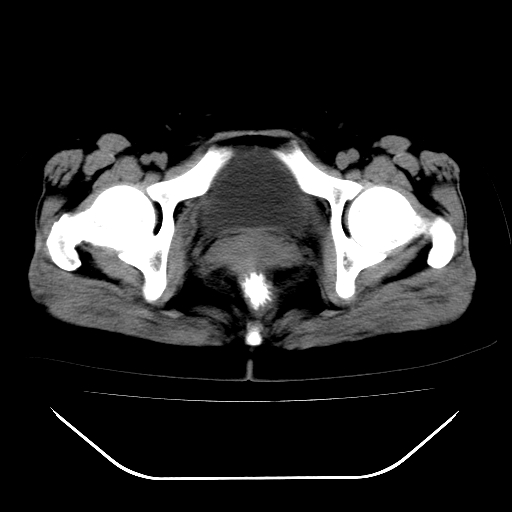

女,48岁,肛门坠胀感一年,肠镜未见异常。

子宫明显增大,形态不规则。多考虑:子宫肌瘤!

子宫明显增大,形态不规则,  盆腔积液 结合临床考虑:1子宫肌瘤, 2  盆腔炎。

道格拉斯窝积液考虑慢性盆腔炎,宫腔少量积液,子宫肌瘤不好说,建议增强。